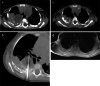

Materials and methods: We collected data of children with thoracic mesenchymal hamartomas who were treated at our institution from 2005 to 2020 using various percutaneous techniques. Techniques included radiofrequency thermoablation, microwave thermoablation (microwave thermoablation) and cryoablation.

Results: Five children were treated for chest wall hamartomas; one child showed bilateral localization of the mass. Two children underwent microwave thermoablation, one radiofrequency thermoablation and two cryoablation; one child treated with cryoablation also had radiofrequency thermoablation because mass volume increased after the cryoablation procedure. The median reduction of tumor volume was 69.6% (24.0-96.5%). One child treated with microwave thermoablation showed volumetric increase of the mass and underwent surgical removal of the tumor. No major complication was reported.

Conclusion: Percutaneous ablation is technically feasible for expert radiologists and might represent a valid and less invasive treatment for chest wall chondroid hamartoma, avoiding skeletal deformities.